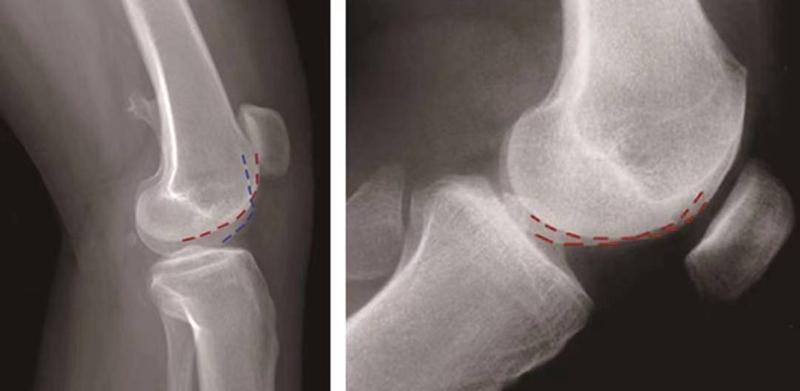

①交叉征:

H.Dejour在1987年介绍了股骨滑车发育不良在膝关节标准侧位X线片的特殊表现,描述了交叉征(crossing sign)。在股骨滑车发育不良的膝关节标准侧位像上,股骨滑车沟基底线会与股骨外髁的轮廓线相交叉,即为交叉征(图11),意味着股骨滑车发育平坦。

图11 交叉征

②突起征:

H.Dejour在1996年提出突起征(spur或bump)或滑车近端突起征(supratrochlear spur),是指在膝关节标准侧位像上,股骨滑车沟基底线的最高点位于股骨前方皮质延长线的前方(图12)。这种征象的实质是股骨滑车近端的整体抬高。在膝关节屈曲早期,髌骨必须越过滑车近端的突起才能进入股骨滑车,因此,容易出现髌骨向外脱位。如果突起征>5mm即为异常,意味着股骨滑车基底高于股骨外髁的轮廓。

图12 突起征

③*轨双**征(或称为双线征):

是指在膝关节标准侧位像上,代表股骨内外侧滑车的两条线分开,呈*轨双**样(图13)。它的出现提示股骨内侧滑车发育低平,导致它的前缘出现晚于外侧滑车。

图13 *轨双**征